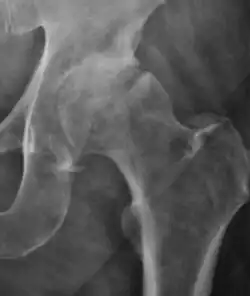

Projectional radiography ("X-ray") is the first imaging technique of choice in hip pain, not only in older people with suspected osteoarthritis but also in young people without any such suspicion. In this case plain radiography allows categorization as normal hip or dysplastic hip, or with impingement signs, pincer, cam, or a combination of both.[1]

X-Ray

Projectional radiography ("X-ray") is currently useful not only in older people in whom osteoarthritis of the hip is suspected but also in younger people without osteoarthritis, who are being evaluated for femoroacetabular impingement (FAI) or hip dysplasia.[1]

Plain radiography allows us to categorize the hip as normal or dysplastic or with impingement signs (pincer, cam, or a combination of both). Besides these, pathologic processes like osteoarthritis, inflammatory diseases, infection, or tumors can also be identified (Figure 1).[1]

Figure 1.

-

Radiography in normal hip -

X-ray in pincer impingement type of hip dysplasia -

X-ray of cam -

Hip in osteoarthritis -